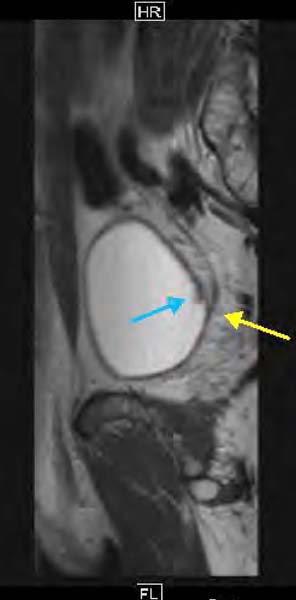

私自身がんになって<2>カルテで分かった膀胱がんの悪性度